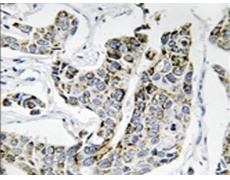

IHC positive control: |

Human breast carcinoma tissue |